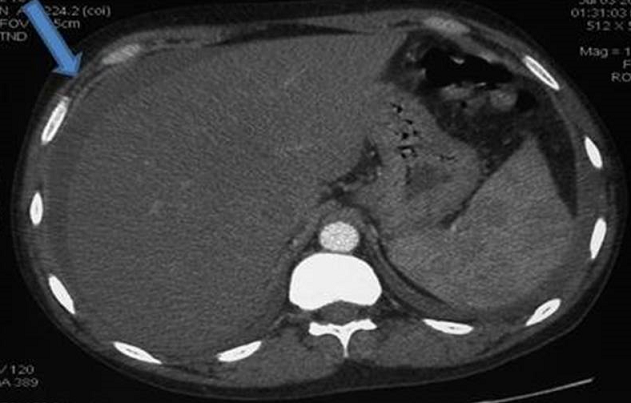

We report the case of a 42-year old male patient was admitted to our hospital because of a two weeks history of severe dry cough and right upper quadrant pain. He had been diagnosed as LES with diffuse proliferative lupus nephritis (class IV) in 2006 treated intially by intravenous steroid pulse therapy combined with an immunosuppressant and benefited in 2007 of Hemodialysis. In July 2013, he suffered of constant abdominal pain located at the right upper quadrant with dry cough. C-reactive protein (CRP) was 17 mg/L (normal < 8 mg/L) on admission with positive antinuclear antibodies title at 1/1280. The chest-abdominal computed tomography scan showed a pleural effusion a regular hepatomegaly with a rim of enhancement involving the right lobe of the liver. No ascites was present and there was no ancillary evidence of cholecystitis. The findings were thought to be most consistent with a perihepatitis. Pleural fluid examination showed an exudative pleural effusion with a negative culture. The diagnosis of perihepatitis associated with SLE complicated by a right pleural effusion was taken. The patient condition was treated with two antibiotics (vibramycin and amikacyn) and oral prednisolone. On review 4 weeks later his pain, cough and the right pleural disappeared. Perihepatitis is a rare disease, normally associated with pelvic inflammatory disease. It has rarely been reported in association with systemic lupus erythematosus (SLE) particularly in patients with lupus hemodialysis nephritis.